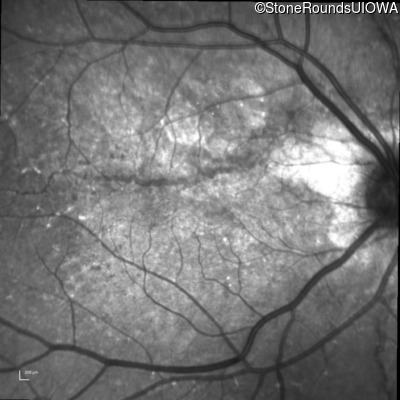

Infrared Fundus Photograph - Right - 20/80

Exemplar